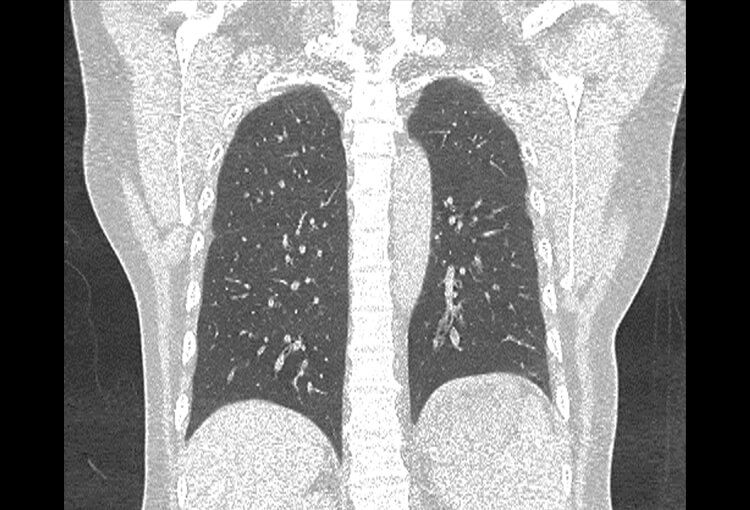

Before and After Denoising

120 kV / 30 mAs / 1mm

Before FBP (Noise 150) VS After ClariCT.AI (Noise 49) 67% Denoising